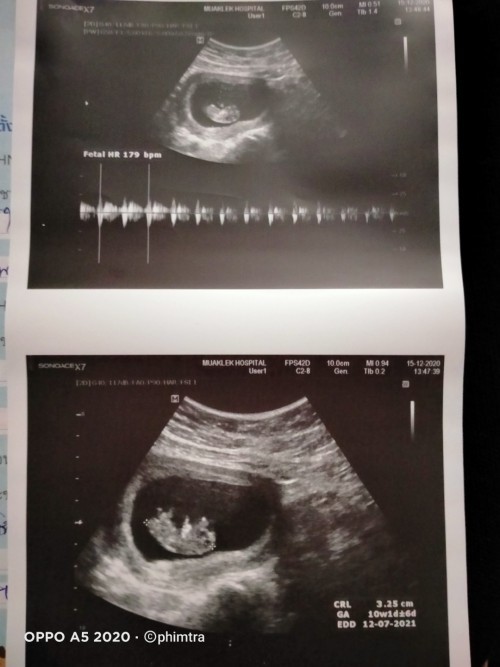

10 w 5 d เป็นตัวแล้วค่ะ

10Wเห็นแล้วค่ะ

ซาวตอน10วีคคะ